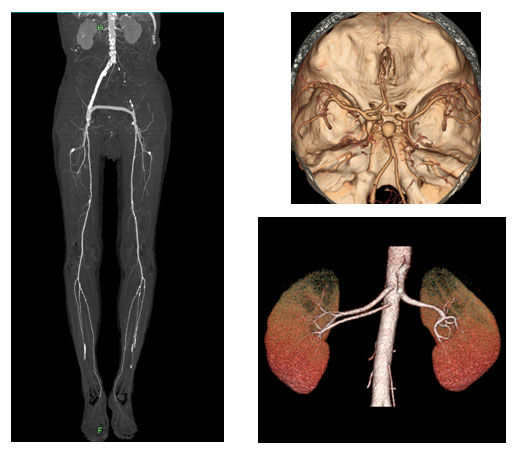

복부 CT(Computed Tomography)는 방사선과 컴퓨터 기술을 결합하여 신체 내부 구조를 3차원으로 시각화하는 영상 진단 방법입니다. 일반적인 X-ray와는 차별화된 측면에서, 복부 CT는 단면 이미지를 연속적으로 수집하여 더욱 정밀한 진단이 가능합니다. 그러므로 의사들은 이를 활용해 매우 다양한 복부 질환을 진단하며, 이를 통해 조기 발견 및 치료 방안을 신속하게 결정할 수 있습니다.

복부 CT 장비는 링 형태의 기계 내부에 방사선 투사 장치와 감지기가 내장되어 있습니다. 환자는 이 링 내부에 누워 있으며, 장비가 부드럽게 회전하면서 단면 이미지를 촬영합니다. 각각의 이미지들은 컴퓨터 소프트웨어에서 합쳐져 3차원의 고해상도 이미지를 생성하게 됩니다. 이러한 과정을 통해 의사는 대장, 간, 췌장, 신장 등 복부 각 장기의 상태를 면밀히 살펴볼 수 있습니다.

복부 CT는 수많은 질환을 진단하는 데 사용되며, 특히 몇 가지 주요 질병은 CT 검사에서 뚜렷하게 드러납니다. 이번 섹션에서는 복부 CT로 진단할 수 있는 대표적인 질병을 살펴보겠습니다. 이들 질병은 모두 환자에게 심각한 영향을 미칠 수 있는 만큼, 조기 발견이 무엇보다 중요합니다.